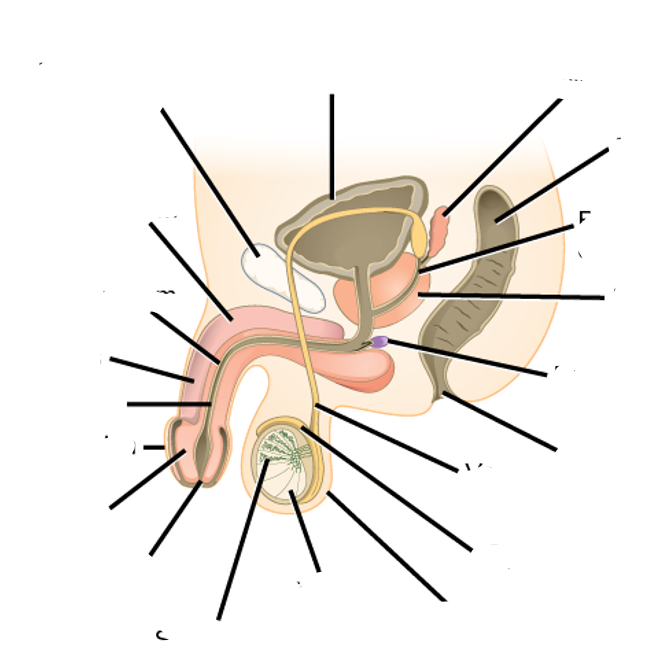

what do this images show